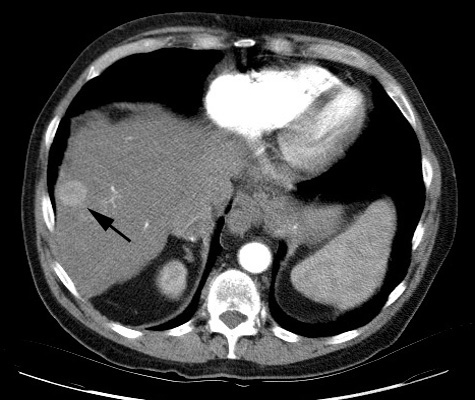

We first confirm that the color of noise can impact

the detectability of objects in an image dominated by noise. One of the common

tasks of radiologists using CT is to identify tumors, such as the one in Figure

8, annotated by a black arrow [6]. The tumor is a small round object that is

slightly brighter than the background liver tissue. Because it is not texture

but a uniform increase in signal that defines the tumor, it consists of mostly

low frequencies. Therefore, filtering away high frequencies would not

significantly reduce the visibility of the tumor, but it could filter away

undesired noise. To test the difference this has on different colors of noise,

we “hide” a tumor-like object in a uniform background by injecting enough white

or blue noise so that the object is lost among the noise. A video was created

in Matlab to illustrate our ability to find this tumor as the image is

increasingly blurred by a low-pass filter (createNoiseMovie.m).

Figure 8. Subtle liver tumor.